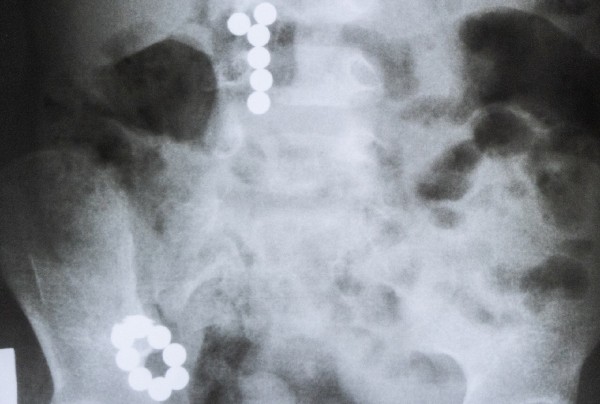

В Челябинске трехлетний ребенок проглотил 14 магнитов. Новомодная игрушка стала причиной операции.

Родители привезли сына в больницу после того, как малыш проглотил детали от игрушки. Снимок показал, что шесть магнитов еще находятся в желудке, а остальные восемь – уже перешли в 12-перстную кишку.

Медики приняли решение о том, что достать их эндоскопическим методом уже невозможно, поэтому нужно незамедлительно оперировать.

«Ребенка подготовили к операции, был выполнен небольшой лапаротомный срединный разрез, и магниты были извлечены. Колечко, которое находилось в толстом кишечнике, удалось извлечь без вскрытия, мы его вручную по кишечнику переместили к прямой кишке и вытащили», – рассказала детский хирург отделения гнойной хирургии Челябинской областной детской клинической больницы Светлана Климова.

Хирург также отметила, что, к счастью, магниты притянулись друг к другу и перемещались по организму ребенка вместе, это упростило задачу по извлечению.

Кроме того, ребенку повезло, что в руки к врачам он попал не позже двух часов после проглатывания. Дело в том, что, притягиваясь друг к другу, магниты повреждают стенки желудочно-кишечного тракта – это может привести к образованию перфорации и выходу содержимого кишечника в брюшную полость.